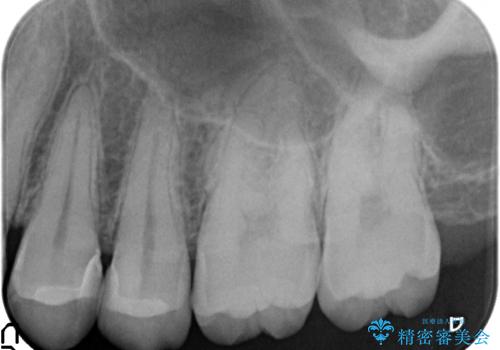

X線撮影によりわかる、内在する虫歯治療

X線検査により、歯の変色部は大きな虫歯が内在することがわかりました。

マイクロスコープで神経を保存できるよう丁寧に虫歯を除去したのちセラミックインレーにて高精度な修復を行っていきます。